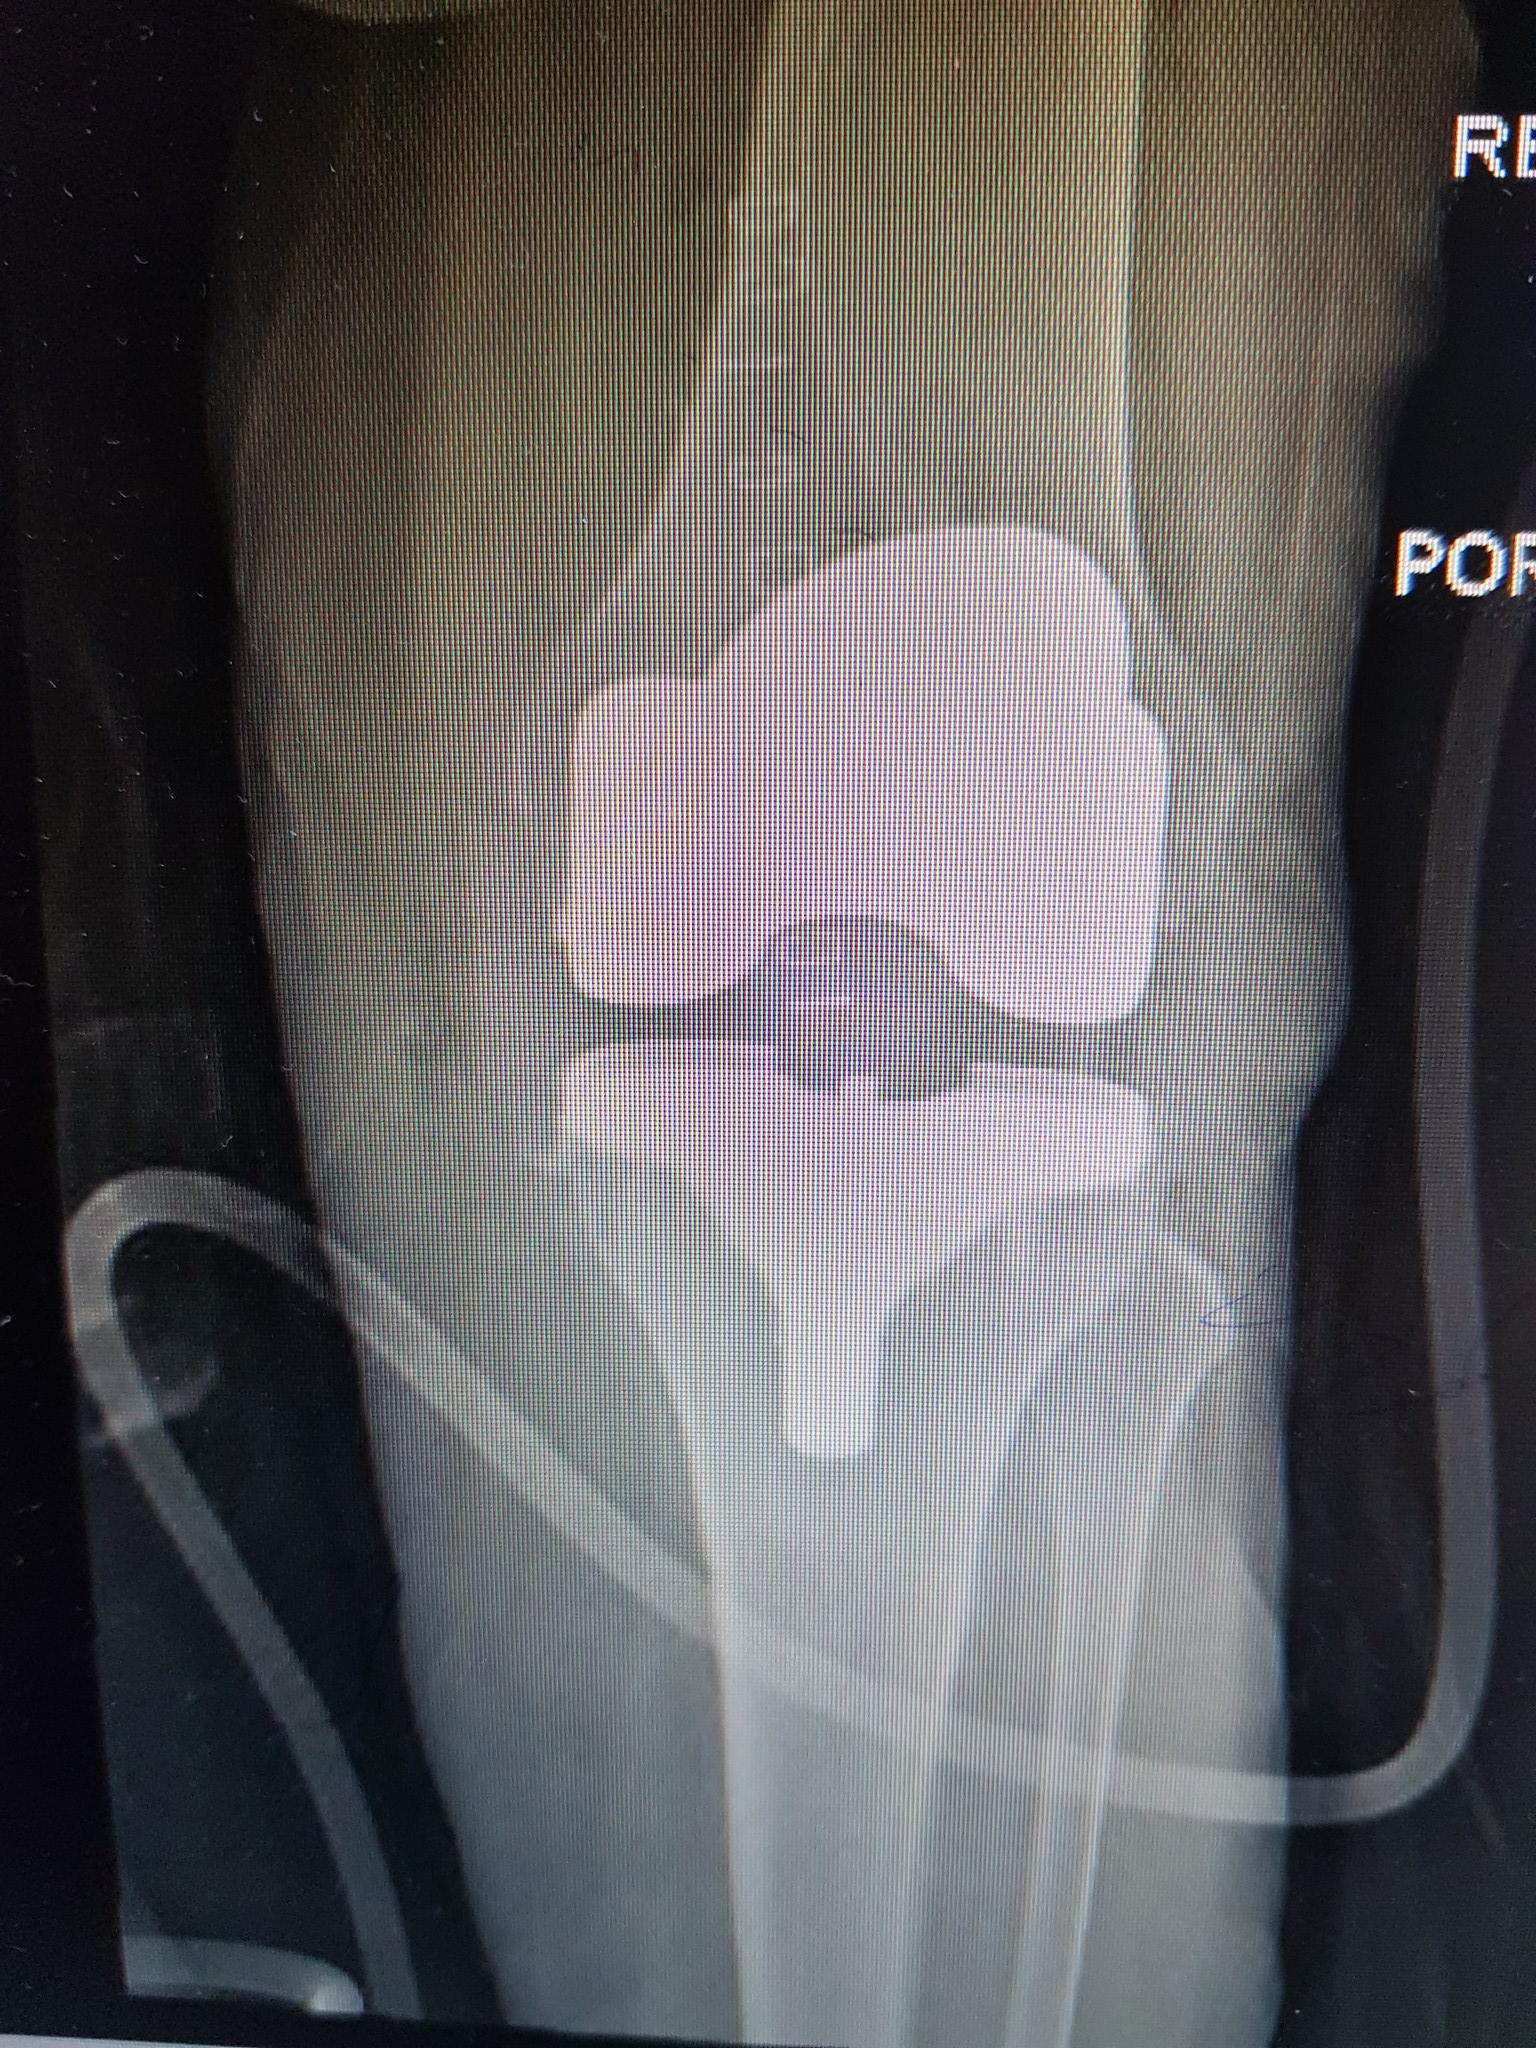

زراعة المفاصل الصناعية ورك و

جراحة العظام والمفاصل